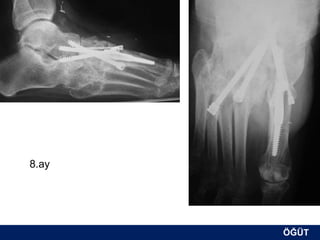

OLGU No 3

FK, 58y, ♂

8.ay

ÖĞÜT